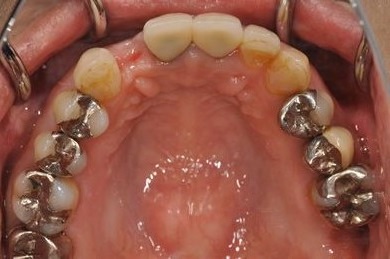

インプラントの症例写真 IMPLANT

骨再生スピードインプラント治療+セラミック治療

| 治療方針 | 上前歯の欠損部分は、ブロック骨移植により、インプラント治療を可能にする。左下奥の欠損部分は、保存不可能な歯を抜歯すると同時にインプラントを埋入し、治療期間を短縮する。 | ||||||||||||||||||||||||||||||||

| 治療内容 | インプラント3本(抜歯即日スピードインプラント、骨移植)、メタルボンドセラミッククラウン5本(メタルボンド用土台1本)、オールセラミッククラウン1本(オールセラミック用土台1本) | ||||||||||||||||||||||||||||||||